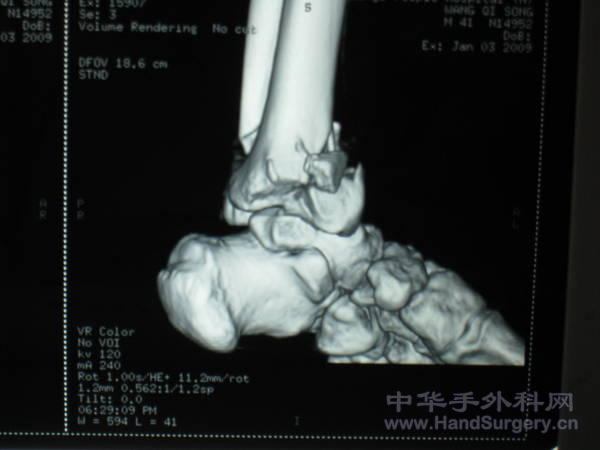

pilon骨折一例-手足外科魏宝富主任作品

这种骨折为从高坠落高能量致的损伤,损伤都较重,对重的有的主张一期行关节融合,如轻的可以行复位内固定,一般都要行植骨。

pilon骨折在哪做都是高难度手术,骨性支架的建立应该最重要,皮肤缺损对手足外科大夫来讲已经不是什么难题 ,希望看到踝关节关节面的x线或ct。

魏主任:你的手术做的很好,但是不知关节面是如何处理的,植骨了吗?是急症做的还是消肿以后做的?切口愈合如何?还有外侧的关节面好像没有处理?

对于此类骨折,手术最关键所在应该是先恢复腓骨解剖位置,其余骨折块做起来较容易些。另外需要注意植骨支撑,再者注意下胫腓关系一定要稳定!不要轻易去做融合!个人理解